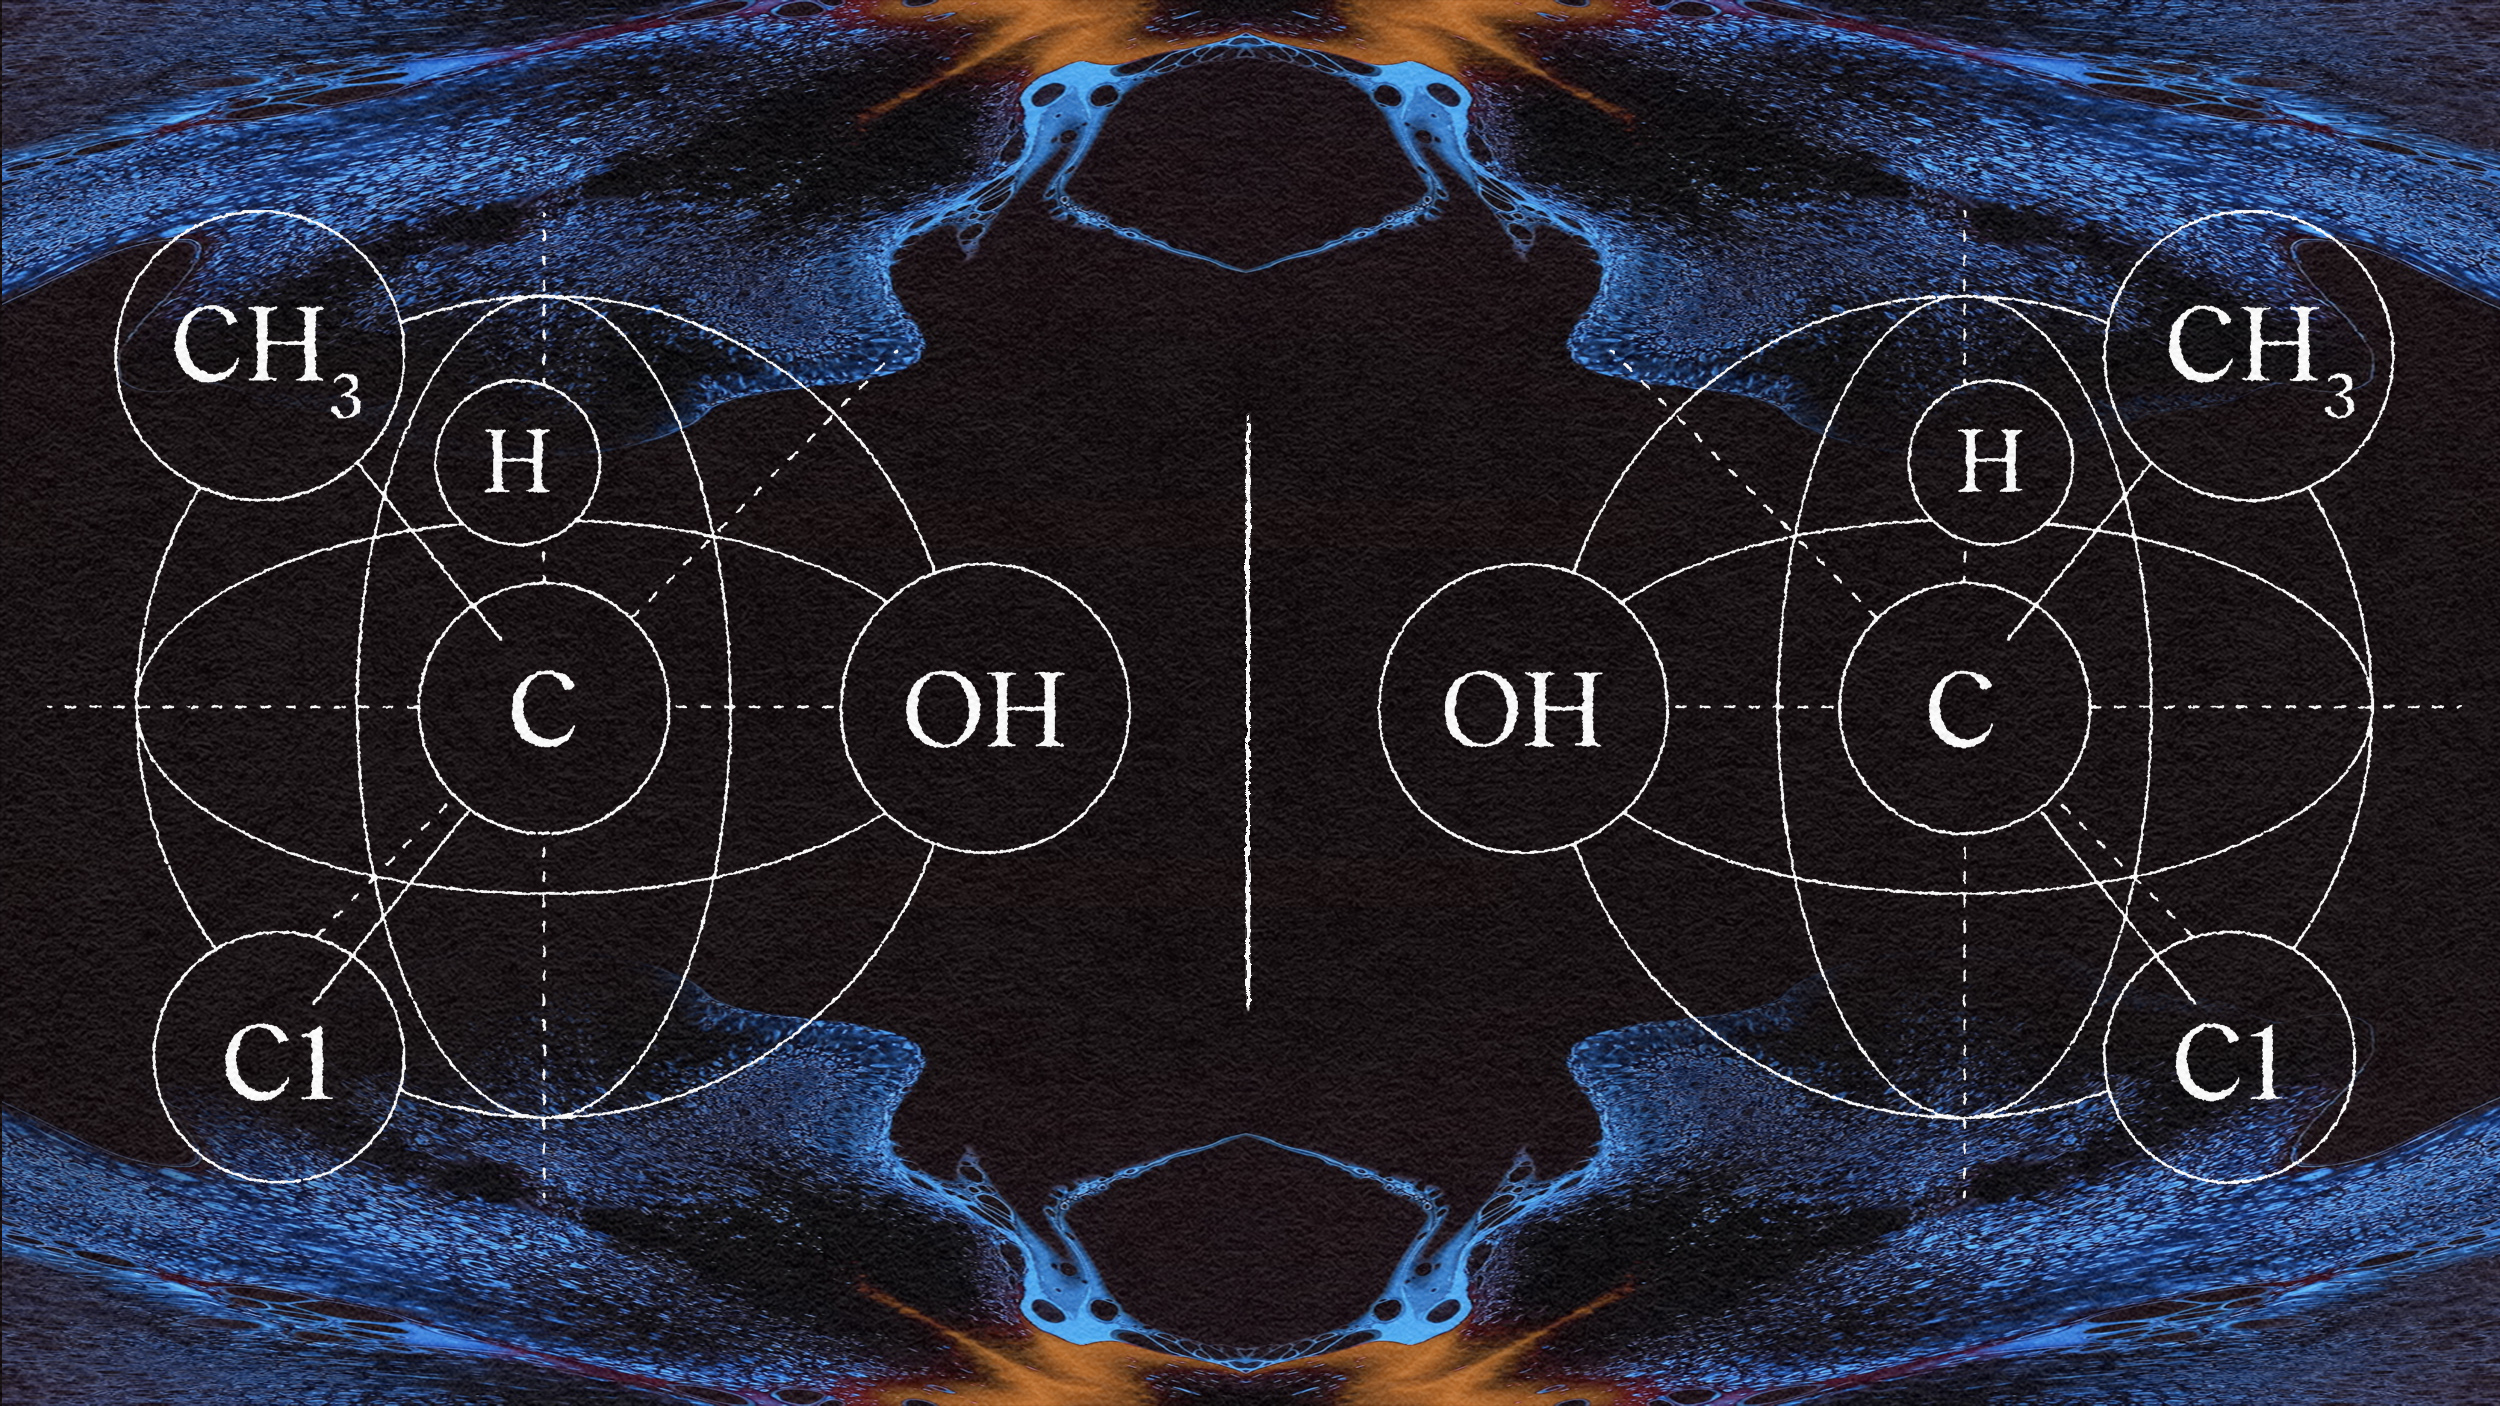

This biochemist is determined to create a new life form by reversing the shape of molecules.

Pain relievers like acetaminophen and ibuprofen are made with chemicals derived from oil. Scientists have shown how to make them from trees.